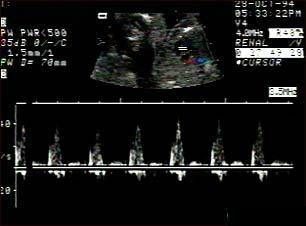

Ecografia fetala